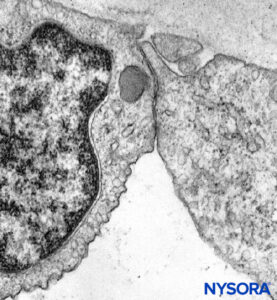

With electron microscopy, perineurial cells are seen as thin sheets of cytoplasm containing small amounts of endoplasmic reticulum, filaments, and numerous endocytic vesicles. Tight junctions and gap junctions between adjacent cells within the same layer of perineurium are also observed. Similar tight junctions may also appear between successive layers of the perineurium when their cells are in close proximity. Tight junctions in the inner layers of the perineurium and tight junctions in endoneurial capillaries form a blood-nerve barrier structure (Figures 17 and 18). The blood-nerve barrier is not equivalent to the blood-brain barrier as the blood-brain barrier astrocytes help regulate the flow of compounds between blood and the brain. The perineural cells are metabolically active, and their cytoplasms contain enzymes like ATPase (adenosine triphosphatase), 5-nucleotidase, and so on. These cells probably play a role in maintaining electrolyte and glucose balance around the nerve cells.

FIGURE 17. Endoneurium and capillaries inside fascicles of peripheral nerves. Transmission electron microscopy. Magnification ×3000. (Reproduced with permission from Reina MA, Arriazu R, Collier CB, et al: Electron microscopy of human peripheral nerves of clinical relevance to the practice of nerve blocks. A structural and ultrastructural review based on original experimental and laboratory data. Rev Esp Anestesiol Reanim. 2013 Dec;60(10):552-562.)

FIGURE 18. Endothelial cell from intrafascicular capillary. Transmission electron microscopy. Magnification ×20,000. (Reproduced with permission from Reina MA, López A, Villanueva MC, et al: The blood-nerve barrier in peripheral nerves. Rev Esp Anestesiol Reanim. 2003 Feb;50(2):80-86.)